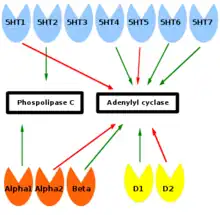

Many antidepressant drugs acutely increase synaptic levels of the monoamine neurotransmitter, serotonin, but they may also enhance the levels of norepinephrine and dopamine. The observation of this efficacy led to the monoamine hypothesis of depression, which postulates that the deficit of certain neurotransmitters is responsible for depression, and even that certain neurotransmitters are linked to specific symptoms. Normal serotonin levels have been linked to mood and behaviour regulation, sleep, and digestion; norepinephrine to the fight-or-flight response; and dopamine to movement, pleasure, and motivation. Some have also proposed the relationship between monoamines and phenotypes such as serotonin in sleep and suicide, norepinephrine in dysphoria, fatigue, apathy, cognitive dysfunction, and dopamine in loss of motivation and psychomotor symptoms.[33] The main limitation for the monoamine hypothesis of depression is the therapeutic lag between initiation of antidepressant treatment and perceived improvement of symptoms. One explanation for this therapeutic lag is that the initial increase in synaptic serotonin is only temporary, as firing of serotonergic neurons in the dorsal raphe adapt via the activity of 5-HT1A autoreceptors. The therapeutic effect of antidepressants is thought to arise from autoreceptor desensitization over a period of time, eventually elevating firing of serotonergic neurons.[34]

Receptor binding

As of 2012, efforts to determine differences in neurotransmitter receptor expression or for function in the brains of people with MDD using positron emission tomography (PET) had shown inconsistent results. Using the PET imaging technology and reagents available as of 2012, it appeared that the D1 receptor may be underexpressed in the striatum of people with MDD. 5-HT1A receptor binding literature is inconsistent; however, it leans towards a general decrease in the mesiotemporal cortex. 5-HT2A receptor binding appears to be dysregulated in people with MDD. Results from studies on 5-HTT binding are variable, but tend to indicate higher levels in people with MDD. Results with D2/D3 receptor binding studies are too inconsistent to draw any conclusions. Evidence supports increased MAO activity in people with MDD, and it may even be a trait marker (not changed by response to treatment). Muscarinic receptor binding appears to be increased in depression, and, given ligand binding dynamics, suggests increased cholinergic activity.[60]

Four meta analyses on receptor binding in depression have been performed, two on serotonin transporter (5-HTT), one on 5-HT1A, and another on dopamine transporter (DAT). One meta analysis on 5-HTT reported that binding was reduced in the midbrain and amygdala, with the former correlating with greater age, and the latter correlating with depression severity.[61] Another meta-analysis on 5-HTT including both post-mortem and in vivo receptor binding studies reported that while in vivo studies found reduced 5-HTT in the striatum, amygdala and midbrain, post mortem studies found no significant associations.[62] 5-HT1A was found to be reduced in the anterior cingulate cortex, mesiotemporal lobe, insula, and hippocampus, but not in the amygdala or occipital lobe. The most commonly used 5-HT1A ligands are not displaced by endogenous serotonin, indicating that receptor density or affinity is reduced.[63] Dopamine transporter binding is not changed in depression.[64]